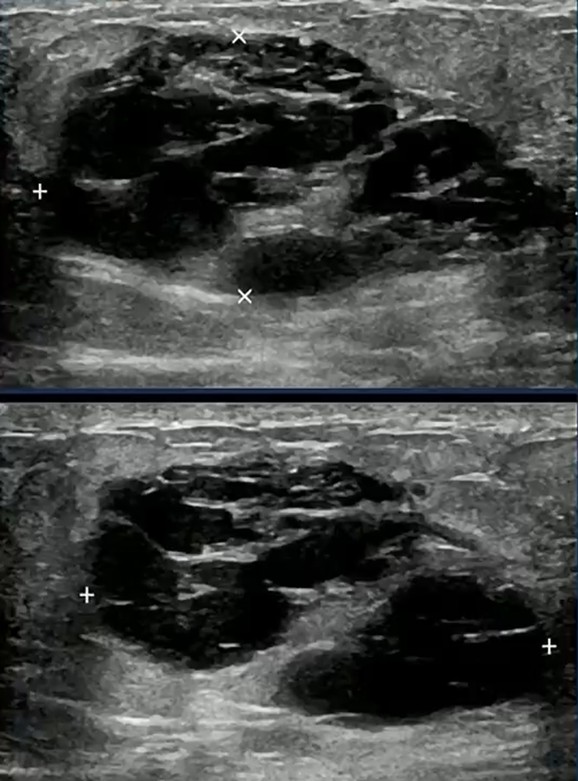

Diagnostic Trap! Consider the following scenario: two patients, both 39, both pregnant, both presenting with a mixed solid and cystic mass. One proves to be a lactating adenoma.

The other is triple-negative breast cancer. Imaging alone may not reliably separate the two.

This is the core interpretive hazard in special populations; pattern recognition must be paired with disciplined skepticism.

Pattern → Constraint → Advantage: Lactating adenomas frequently resemble fibroadenomas on imaging. Mixed morphology and rapid growth can overlap with aggressive cancers, limiting imaging specificity. Thoughtful targeting for biopsy and early tissue diagnosis convert uncertainty into clarity.